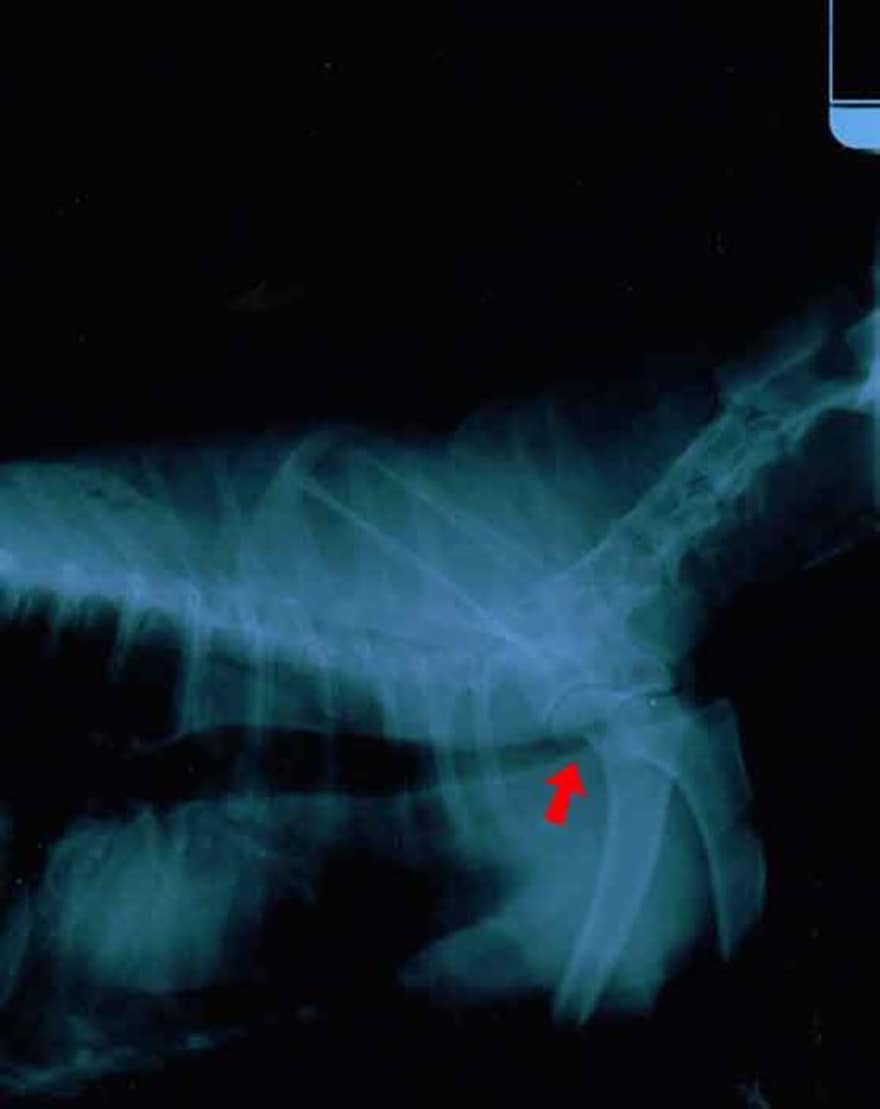

Tracheal Collapse Dog With Collapsed Trachea What To Feed A Dog With A Collapsed Trachea Collapsing trachea is a common cause of coughing in small and toy breed dogs, especially in the yorkshire terrier, toy poodle, chihuahua, pomeranian and shih tzu. Dogs with tracheal collapse may also experience loss of appetite or weight loss. Dogs need about 500 mg of glucosamine per day per 25 lbs of body weight. The compromised ability to breathe due. What To Feed A Dog With A Collapsed Trachea.